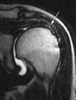

Postoperative defect